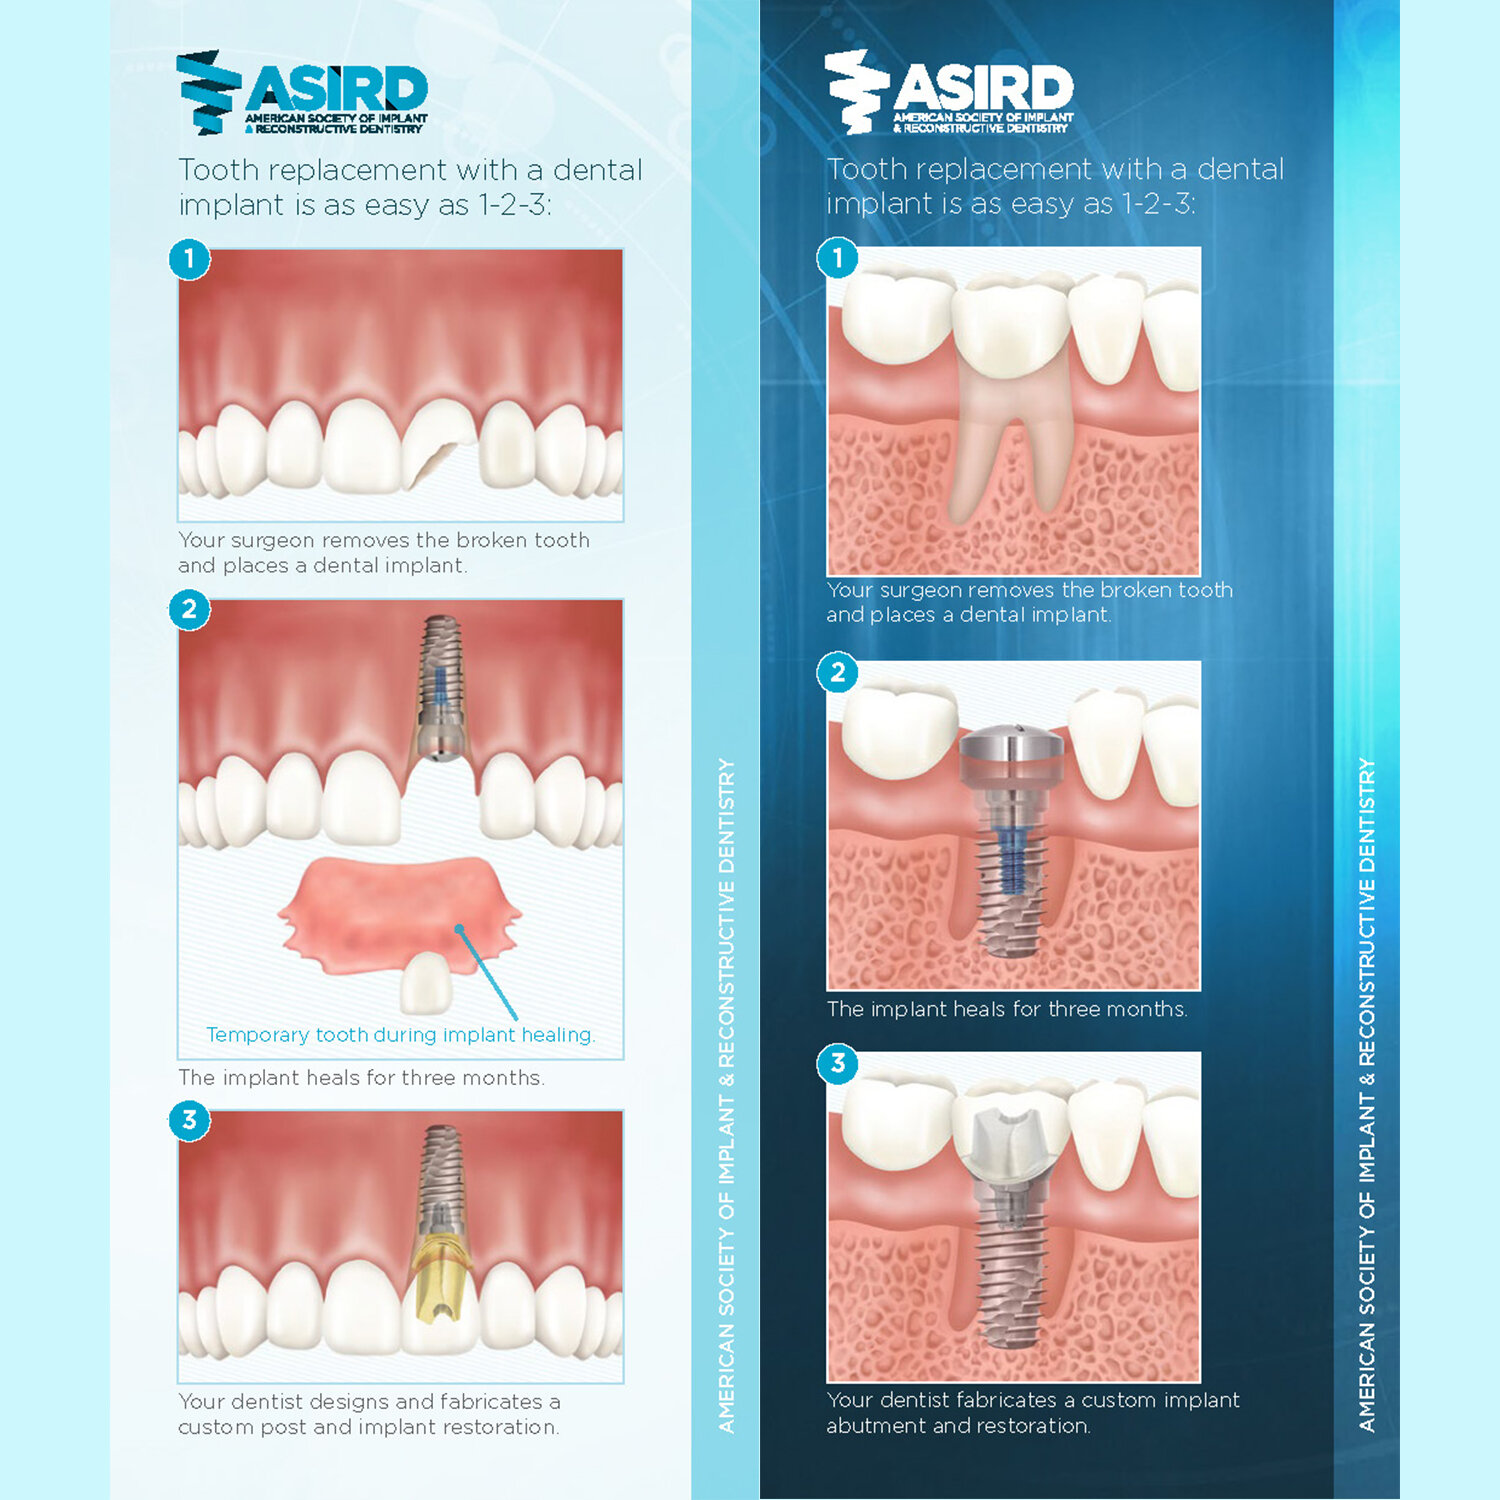

![Dental implant patient brochure]()

Dental implant patient brochure